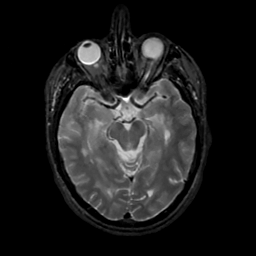

MR Study #10, April 28, 1991 -- Slice #20